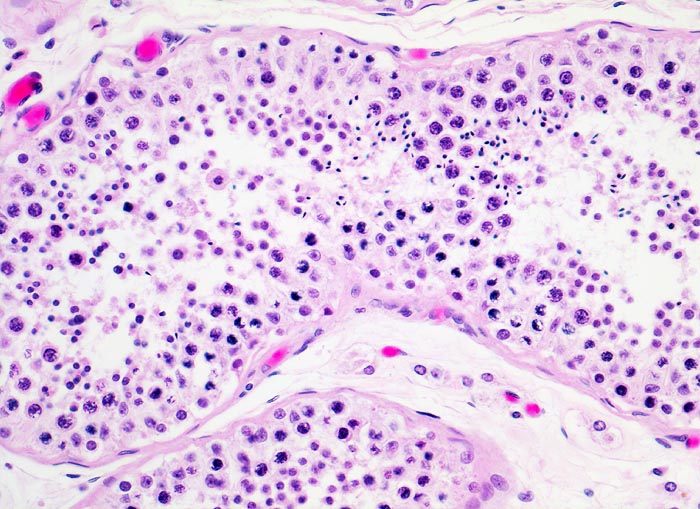

PathoPic ID 4121 - ausreifende Spermiogenese

ausreifende Spermiogenese

Normalbefund

Hoden

Genitalorgane, männlich

Normal ausreifende Spermiogenese

Histologie

200

43

männlich